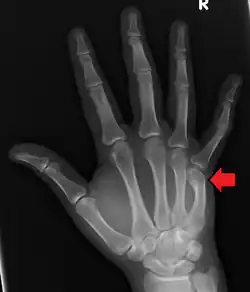

| Apresentação de uma fratura da cabeça do quinto metacarpo | |

A fratura de um boxeador é a fratura do quinto osso metacarpo da mão, próximo à articulação do dedo. Ocasionalmente, também é usado para se referir a fraturas do quarto metacarpo. Os sintomas incluem dor e articulação dos dedos deprimida. Classicamente, ocorre depois que uma pessoa atinge um objeto com o punho fechado. A junta é então dobrada em direção à palma da mão.[1] O diagnóstico geralmente é suspeitado com base nos sintomas e confirmado com raios-X.[1]

O diagnóstico por exame médico é o mais comum, geralmente confirmado por raios X. O raio X é usado para mostrar a fratura e suas angulações. Uma tomografia computadorizada pode ser feita em casos muito raros para fornecer uma imagem mais detalhada.[5]